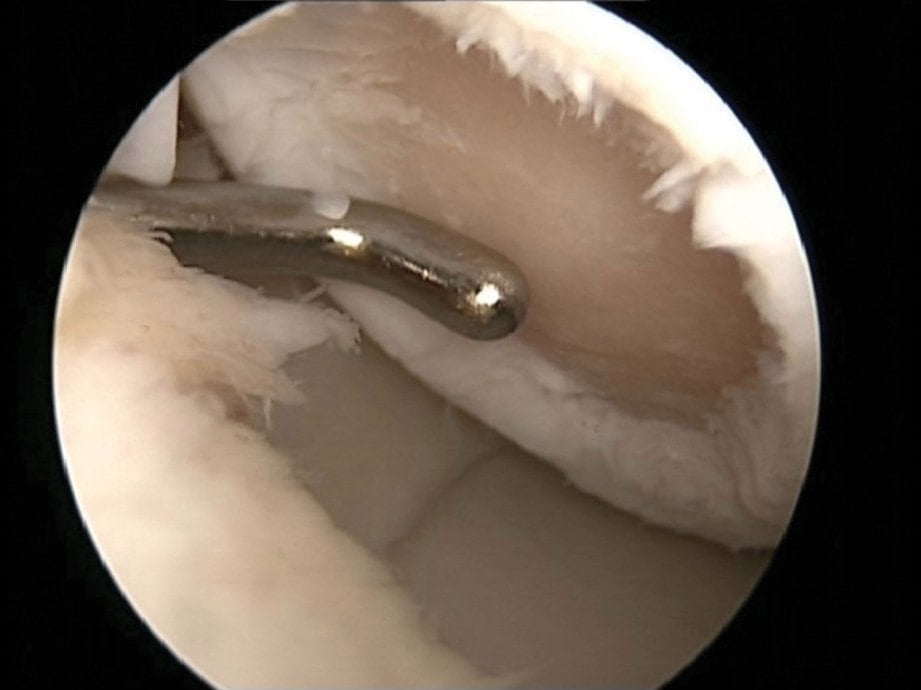

Rawatan Fisioterapi untuk Lutut Chondromalacia - PORTAL MyHEALTH

Rawatan Fisioterapi untuk Lutut Chondromalacia - PORTAL MyHEALTH

Rawatan Fisioterapi untuk Lutut Chondromalacia - PORTAL MyHEALTH

Rawatan Fisioterapi untuk Lutut Chondromalacia - PORTAL MyHEALTH